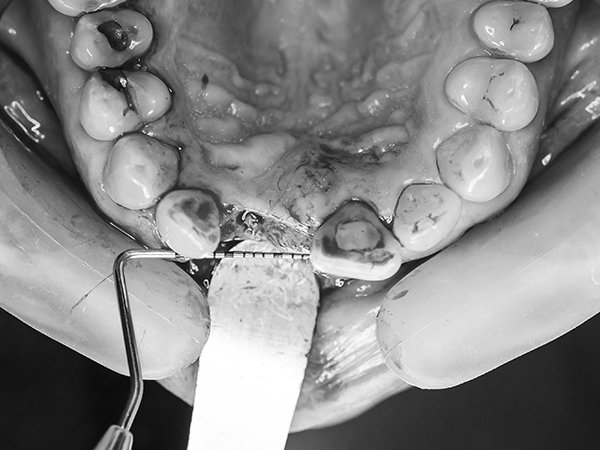

• 사랑니발치

• 사랑니발치는 매복 정도에 따라 난이도가 다릅니다. 정밀 검사를 통해 환자 사랑니 매복상태를 고려하여 정확하고 안전한 발치 치료를 진행합니다.

인골 골이식 사진을 직접 촬영해 환자분에게 확인시켜 드립니다.